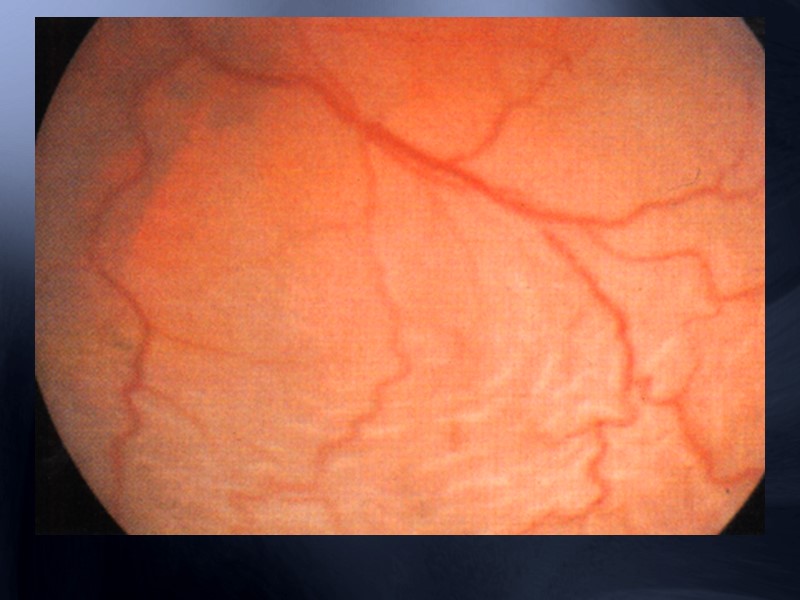

Определяются резко расширенные вены с петлями, геморрагии и отек сетчатки

Артериовенозная ф а з а - расширение вен и капиляров, извитость сосудов, множественнные микроаневризмы в центральных отделах с образованием шунтов на фоне участков капиллярной окклюзии